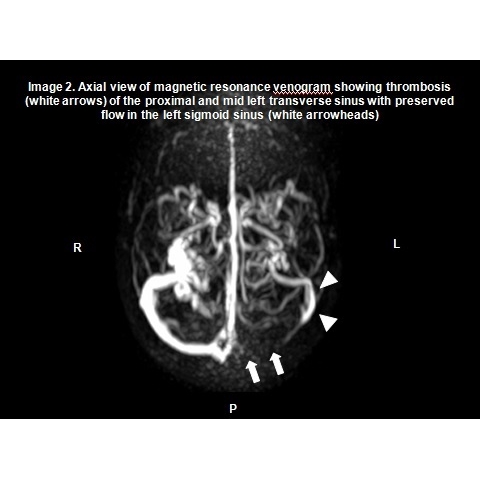

| Post-concussive Syndrome Or Something Deeper, Still? - Page #3 | |||